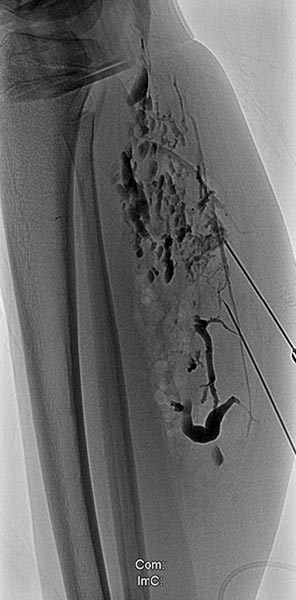

Phlebography after direct puncture of the venous malformation shows a large-lumen drainage vein communicating with the popliteal vein in the popliteal fossa. This must be occluded before sclerotherapy, otherwise the sclerosing agent could unintentionally dislocate through this communication and potentially cause thrombosis of the deep venous system of the leg and/or pulmonary embolism. In addition, there is an ongoing, increased risk of thromboembolism in this patient even outside of sclerotherapy, which can be significantly reduced by occlusion of the communication.